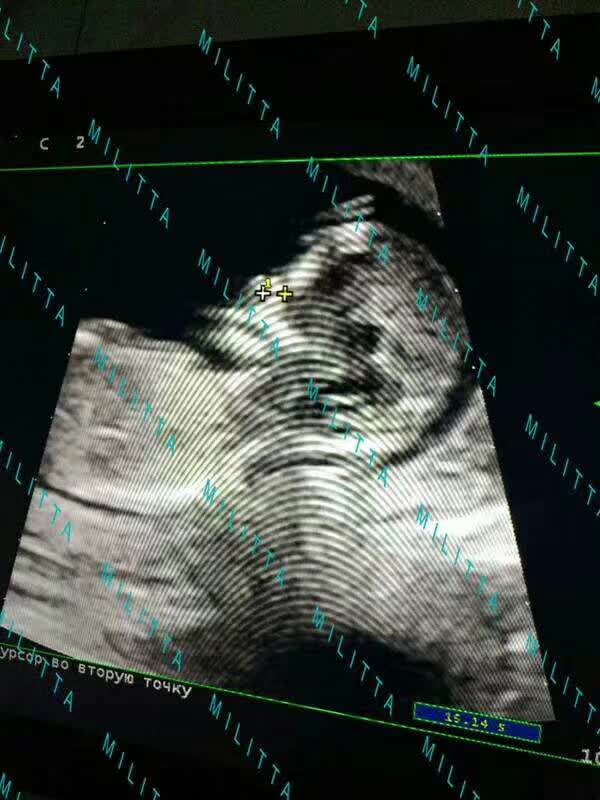

【乌克兰/马丽塔辅助生殖中心】R先生的爱心妈妈孕3个月了,体态仍然轻盈,依然这么美丽。